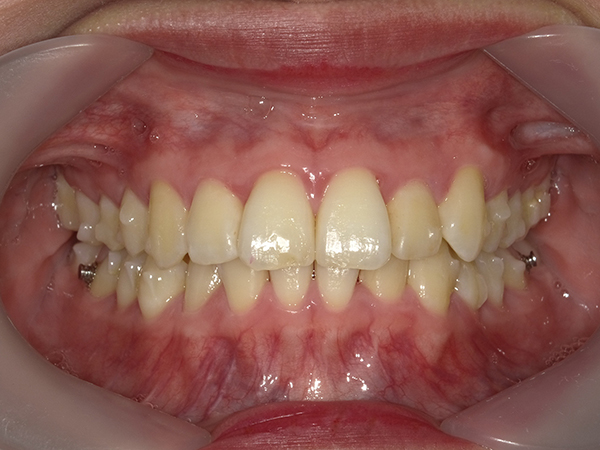

順調に矯正が進んでいき、2020年11月の時点でここまで並んできました。

前回の記事に載せていた、上の歯の隙間も見事に閉じて綺麗になってきました。

噛み合わせ、もだいぶ変わりましたよね!

私は噛み合わせが深く、かちっと噛んだ時下の歯が見えなかったのですが

だいぶ下の歯が見えるようになっています。

また、ブラッシングも圧倒的にしやすくなった為か

歯肉の色や形も綺麗になってきました。